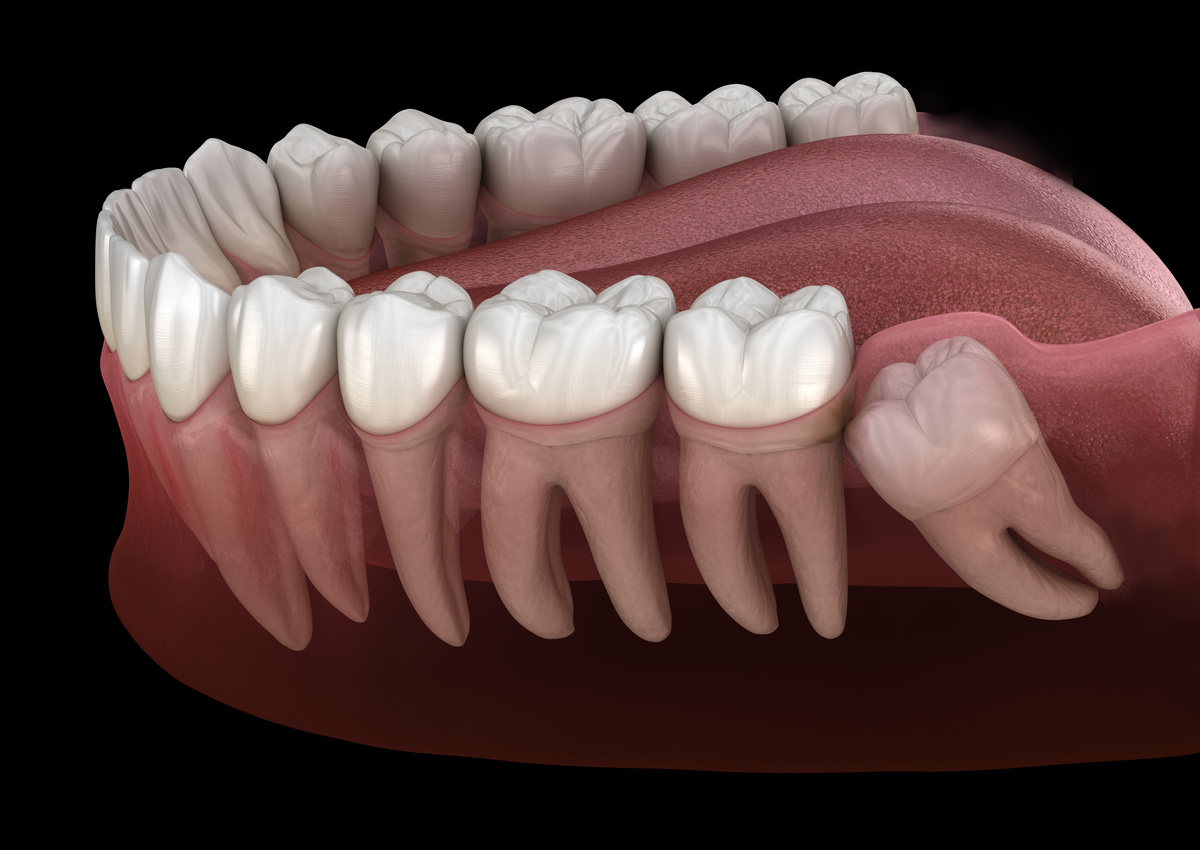

Wisdom tooth extraction is one of the most common oral surgery procedures, and understanding what happens during the process can help ease any concerns you might have. Most people develop four wisdom teeth, which typically emerge between the ages of 17 and 25. These third molars often lack adequate space to grow properly, leading to impaction, crowding, or infection. When wisdom teeth cause problems or show signs of future complications, extraction becomes the best solution to protect your oral health.

Wisdom tooth extraction is one of the most common oral surgery procedures, and understanding what happens during the process can help ease any concerns you might have. Most people develop four wisdom teeth, which typically emerge between the ages of 17 and 25. These third molars often lack adequate space to grow properly, leading to impaction, crowding, or infection. When wisdom teeth cause problems or show signs of future complications, extraction becomes the best solution to protect your oral health.